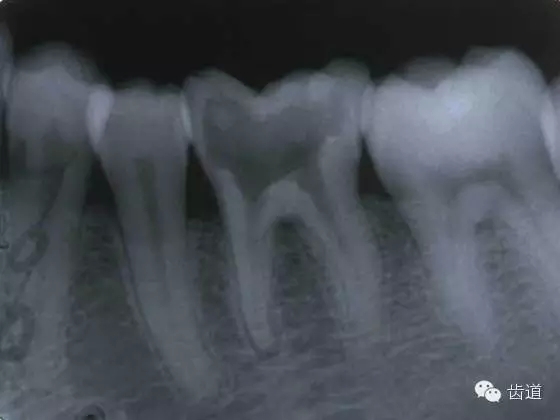

左下7根充后下唇麻木

左下5根管預(yù)備后下唇麻木